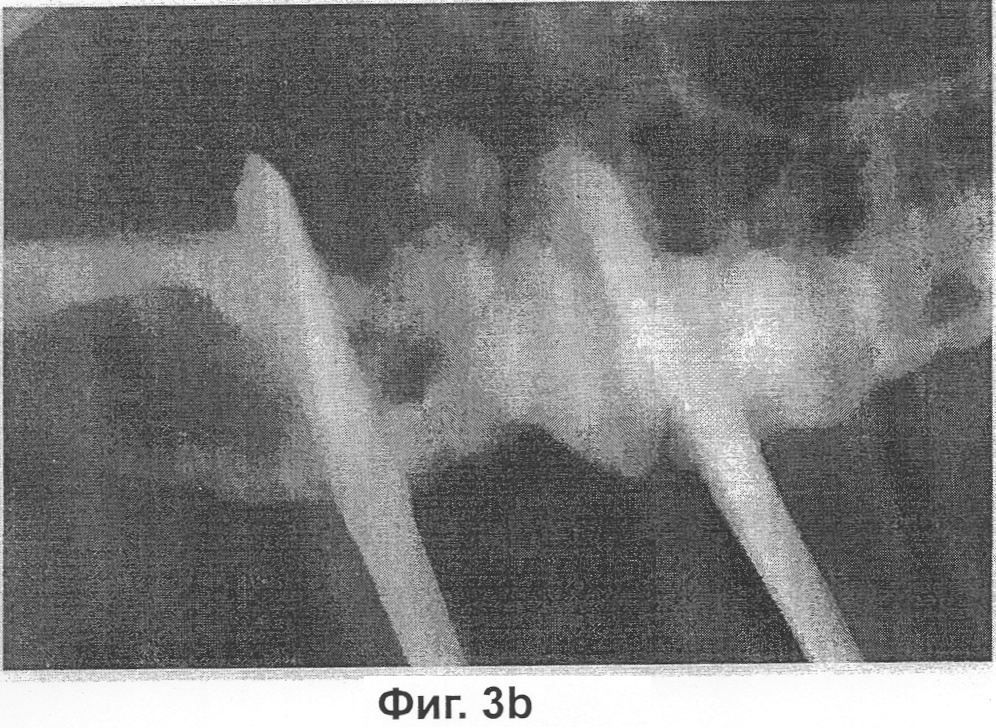

Фиг.3B представляет собой фотографию, на которой показана степень сращения кости в контрольной группе 1, которую оценивали по методу рентгенографического исследования через 6 недель после вытяжения кости, конкретно животным контрольной группы 1 инъецировали только карбоксиметилцеллюлозу и индуцировали вытяжение на 1 мм в сутки в течение 10 суток.

В результате в каждой группе, в которой проводилось вытяжение кости на 2 мм в сутки, за исключением контрольной группы, наблюдалась кальцификация вокруг участка вытяжения челюстной кости, что подтверждалось рентгенограммами, полученными на 3 неделе и на 6 неделе после вытяжения. Между разрезанными частями челюстной кости также наблюдалась рентгенопрозрачная зона, а примыкающие с обеих сторон к разрезанным частям челюстной кости участки соединения различались от группы к группе. На 3 неделю после вытяжения кости в контрольной группе, в которой проводилось вытяжение кости на 1 мм или на 2 мм в сутки без инъекции композиции по настоящему изобретению, как и в другой группе, в которой проводилось вытяжение кости на 2 мм в сутки с инъекцией композиции, рентгенопрозрачная зона была едва различима, тогда как в группе, в которой проводилось вытяжение кости на 1 мм в сутки с инъекцией композиции, наблюдалась массивная рентгеноконтрастная зона. На 6 неделю после вытяжения кости рентгеноконтрастная зона значительно распространилась по направлению к центру участка вытяжения как в контрольной группе, в которой проводилось вытяжение кости на 1 мм в сутки без инъекции композиции по настоящему изобретению, так и в группе, в которой проводилось вытяжение кости на 1 мм или на 2 мм в сутки с инъекцией композиции. Наибольшая рентгеноконтрастная зона наблюдалась в группе, в которой проводилось вытяжение кости на 1 мм в сутки с инъекцией композиции по настоящему изобретению, тогда как в контрольной группе, в которой проводилось вытяжение кости на 2 мм в сутки без инъекции композиции по настоящему изобретению, рентгеноконтрастная зона была едва различима (см. фиг.3-5).

В результате в каждой группе, за исключением контрольной группы 2, в участке вытяжения челюстной кости наблюдалась кальцификация (фиг.3-5). Подтверждено образование рентгенопрозрачной зоны между разрезанными частями челюстной кости и примыкающих к разрезанным частям челюстной кости с обеих сторон участков соединения. На 3 неделю после вытяжения кости в контрольных группах и в получавшей композицию по настоящему изобретению группе 2 рентгенопрозрачная зона была едва различима, тогда как в получавшей композицию по настоящему изобретению группе 1 наблюдалась массивная рентгеноконтрастная зона. На 6 неделю после вытяжения кости в каждой группе, за исключением контрольной группы 2, рентгеноконтрастная зона значительно распространилась по направлению к центру участка вытяжения, а наибольшая рентгеноконтрастная зона наблюдалась в получавшей композицию по настоящему изобретению группе 1.